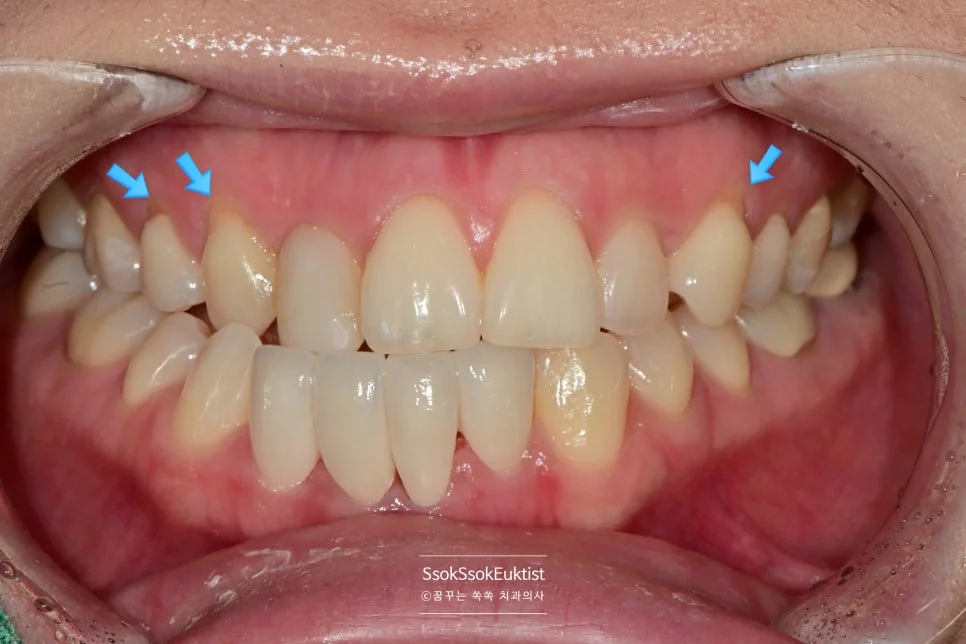

치료 전 정면 교합 사진 — 아래 앞니의 배열 상태 확인

진단 사진 — 가지런하지 않고 정출된 치아, 레진 치료가 되어 있는 부위 (화살표)

아래 앞니의 모양 개선을 원하는 증례입니다.

사진상에서 왼쪽(환자분의 오른쪽) 앞니 두 개가 주변 치아 대비 살짝 솟아 있는 것, 그리고 가지런하지 않은 모양이 내심 오랫동안 마음에 쓰이셨던 것 같습니다.

두 개 치아의 라미네이트를 문의해 주셨었는데요. 이런 치아의 경우 라미네이트는 좋지 않은 선택이라 환자분께 추천드리지 않았습니다.

하악 교합면 사진 — 가장 전방에 위치한 치아 (화살표)

아래 앞니를 더 앞으로 뺄 필요는 없는 상황이었기에 라미네이트가 적합하지 않습니다!

가지런하지 않은 아래 앞니 (화살표) — 크라운 치료가 필요한 상태

모양과 위치를 드라마틱하게 개선하기 위해서는 크라운 치료가 필요하였고, 두 개 치아의 크라운 치료를 계획합니다. 그것도 신경치료 없이!!